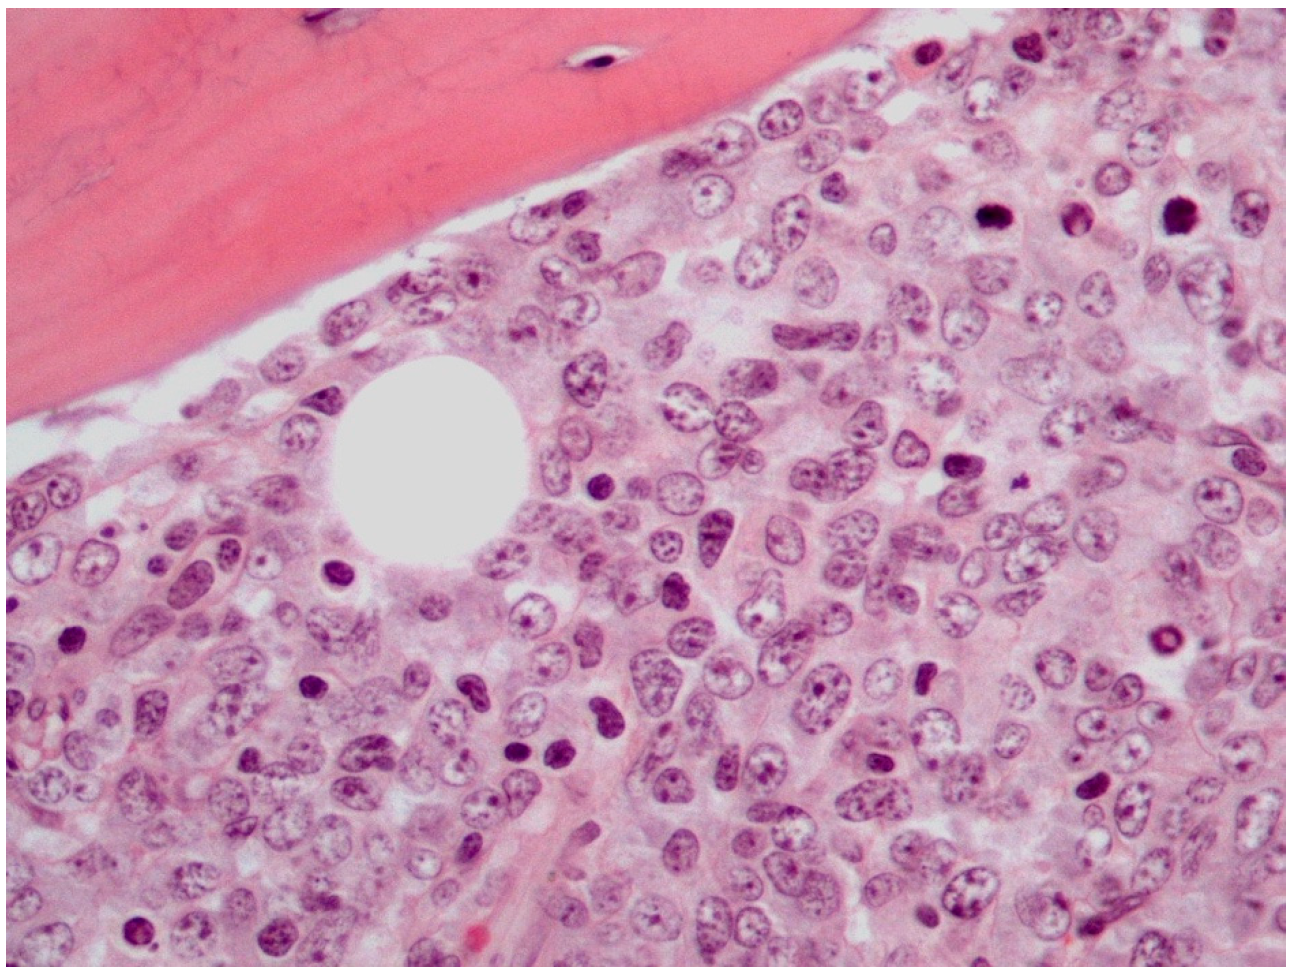

5. Histological Findings